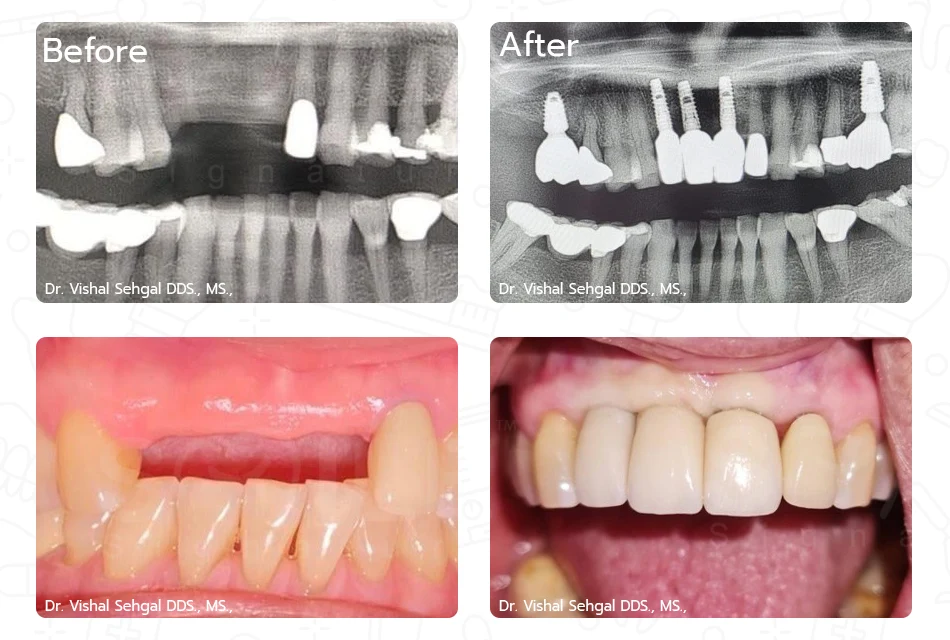

หมอรากฟันเทียม

ทันตแพทย์ วิชาญ แซกัล DDS., MSc.,

เฉพาะทางสาขาสาขาทันตกรรมรากเทียม, สาขาศัลยศาสตร์ช่องปาก และแม็กซิลโลเฟเชียล